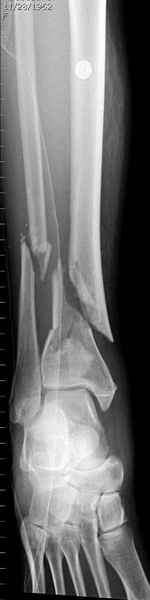

На снимках варианты фиксации малоберцовой:

№ 1 двух лодыжек

№ 2-5 при огнестрельном переломе

№ 6-11 при pilon percutaneus fixation